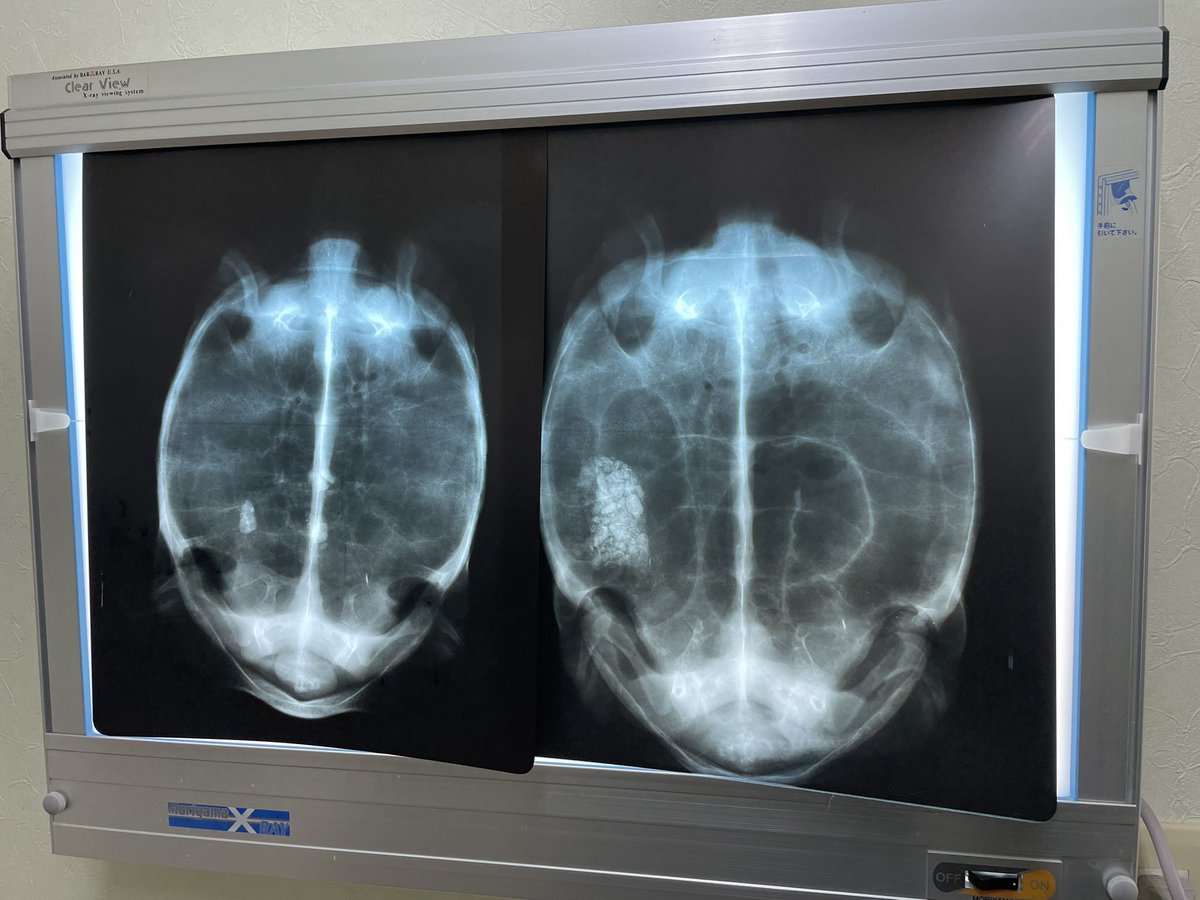

調子が悪いと思ったら、左の個体もめちゃくちゃ食石していました😓明日から投薬と温浴開始ですね💦 右の個体はあと少し🤏頑張れ👍 (レントゲン写真は左右逆になっています🙇) #ホウシャガメ #マダガスカルホシガメ

調子が悪いと思ったら、左の個体もめちゃくちゃ食石していました😓明日から投薬と温浴開始ですね💦

右の個体はあと少し🤏頑張れ👍

(レントゲン写真は左右逆になっています🙇)

#ホウシャガメ

#マダガスカルホシガメ